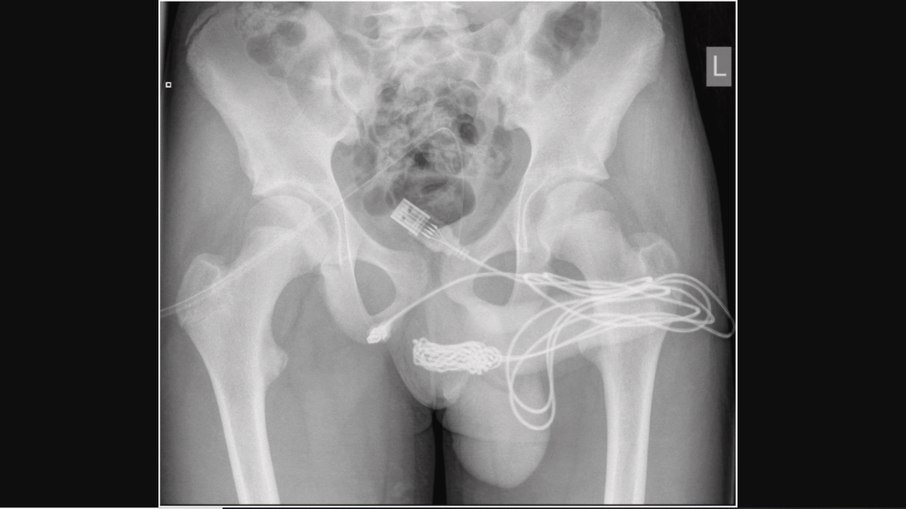

Um garoto de 15 anos ficou com um cabo USB preso no pênis enquanto tentava medir o membro. O adolescente precisou realizar uma cirurgia para remover o fio eletrônico da uretra. O caso ocorreu em Londres, na Inglaterra e a identidade do menino não foi divulgada.

O incidente foi relatado pela revista científica “Urology Case Reports”. O periódico conta que o menino tentou retirar o cabo sozinho, mas acabou ficando com “as duas pontas penduradas em seu membro”. Após urinar sangue, ele procurou os médicos.

A família o levou a um hospital que o encaminhou para o University College Hospital London, para um melhor tratamento. No local, ele necessitou de avaliação urológica terciária urgente e tratamento cirúrgico aberto. Para retirar o cabo USB, foi realizada uma uretrostomia penoescrotal, que é um corte entre a genitália e o ânus do adolescente.

Ainda, segundo o papper, o cabo estava com nós e foi revelado na face proximal da uretra peniana e cortado do restante do cordão. Ambas as pontas do fio foram puxadas com sucesso. Após a cirurgia, o menino recebeu alta no dia seguinte com analgesia simples, antibióticos orais e cateteres suprapúbicos, para a drenagem da urina.